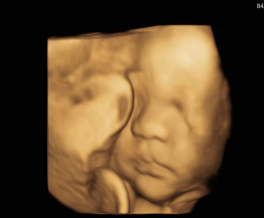

我院超声医学科拥有先进的大型彩超9台,其中有目前世界高端的妇产科超声机GEE8、GEE10、各一台,GEC9两台,全身机迈瑞的Resona7,Reson8各一台,飞利浦650两台,便携式彩超迈瑞M7一台,承担辖区的超声检查、南阳市卧龙区“两癌”乳腺超声筛查及河南省民生实事早孕期NT四维超声筛查及社区体检工作,科室共有工作人员16名,其中副主任医师1人,主治医师4人,住院医师2人,技师3人,护师1名,报告编辑员4名。多次到省级医院进修学习,经验丰富,技术优良。

超声医学科可开展多种超声诊断:包括胎儿系统筛查,妇产科腹部超声,阴道超声检查、子宫畸形三维成像,盆底三维超声、泌尿系、心血管、小儿超声、乳腺、甲状腺超声、腹部超声等多个专业。

我们有着多年的妇产科超声经验,在系统超声方面操作技能娴熟,检查精准细致,技术服务深受被检查者好评。

我院还开展超声医学科VIP,不仅有良好的就医环境,优质的服务态度和精湛的技术,工作站,家属候诊区,孕妈妈区三个屏幕同时显示,让孕妈妈及全家感受新生命的神奇,系统彩超检查限量预约,保障检查质量,预约时间的准确性,最大限度减少孕妈妈等候时间。

我院超声医学科用精湛的技术、耐心细致的服务理念、认真负责的工作态度,为辖区妇女健康和胎儿的优生优育保驾护航!